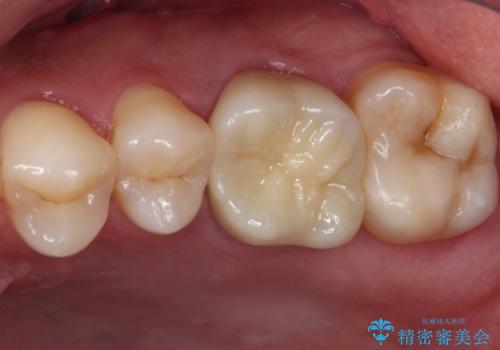

- 歯肉が退縮したためにクラウンの縁や歯根が見えてしまっていることを気にして来院された患者様です。

仮歯に変えた後にオールセラミッククラウンにて補綴することとしました。

治療前と比べてとても自然な前歯となり、患者様には大変満足していただきました。